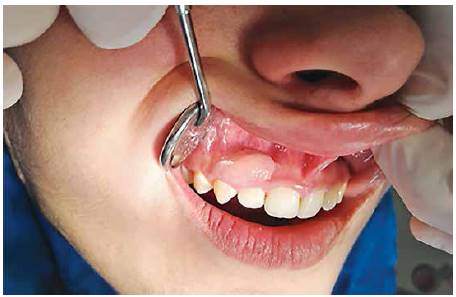

Al realizar el examen intraoral se observa un aumento de volumen de forma ovalada que va desde el margen gingival, abarcando encía adherida hasta muy cerca del fondo de vestíbulo. Esta lesión se extiende desde distal del diente 1.1 hasta mesial del 1.4. A la palpación, su consistencia es muy firme y tiene un color rosa pálido y presenta una base pediculada (Figura 1 y 2).

Se observa higiene oral deficiente y lesiones activas cervicales en dientes anteriosuperiores.